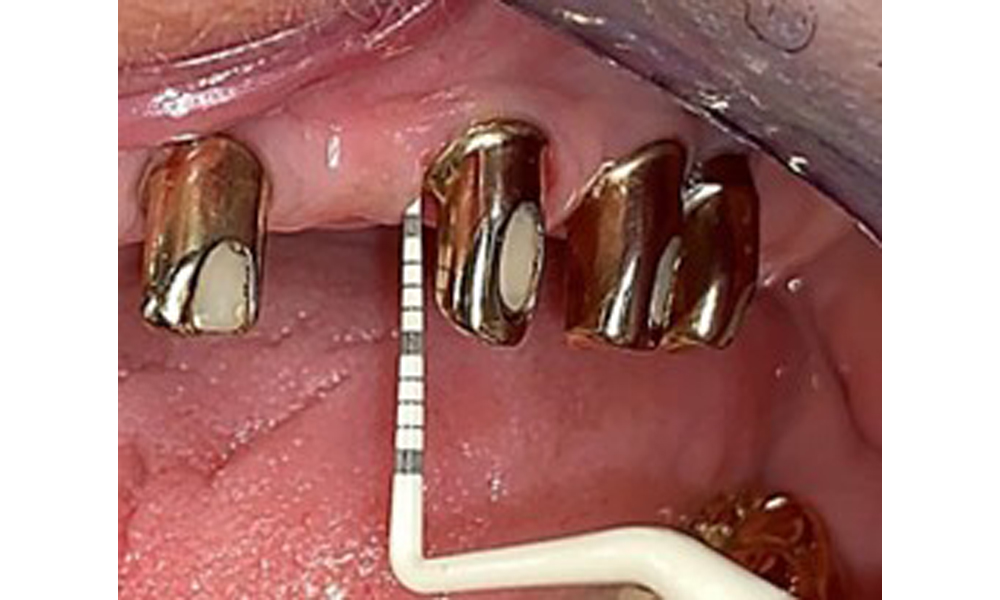

Occlusal view: Maxilla with tooth and implant-supported telescopic prostheses.

Fig. 2: Occlusal view: Maxilla with tooth and implant-supported telescopic prostheses

The patient was fitted with a combined removable maxillary telescopic prosthesis more than 25 years ago (Fig. 1, Fig. 2, Fig. 3) and is very happy with her dentures. The patient has an adequate fixed denture for the mandible (Fig. 4).

The dental findings are as follows: Combined removable implant and tooth-supported telescopic prostheses on implants 15, 13, 21, 23, 24, 25 and tooth 11 (Fig. 1, Fig. 2, Fig. 3). The patient was fitted with a fixed mandibular denture. Adequate bridges were present over 37 to 34 and 45 to 47 (Fig. 4), the crown margins were intact and there were no active caries. A composite filling with a marginal gap was present on tooth 43. There was mandibular gingival recession, exposing 1 to 3 mm of root surface. This also applies to 11.